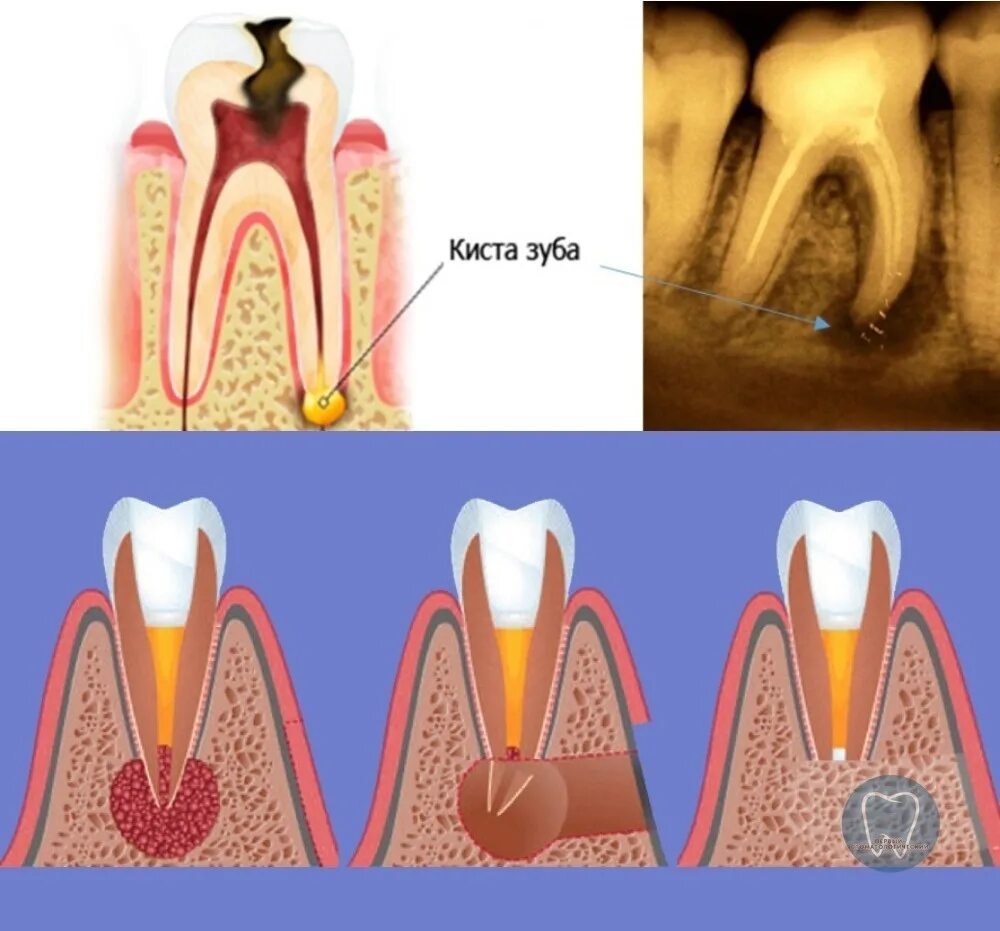

Киста зуба что это